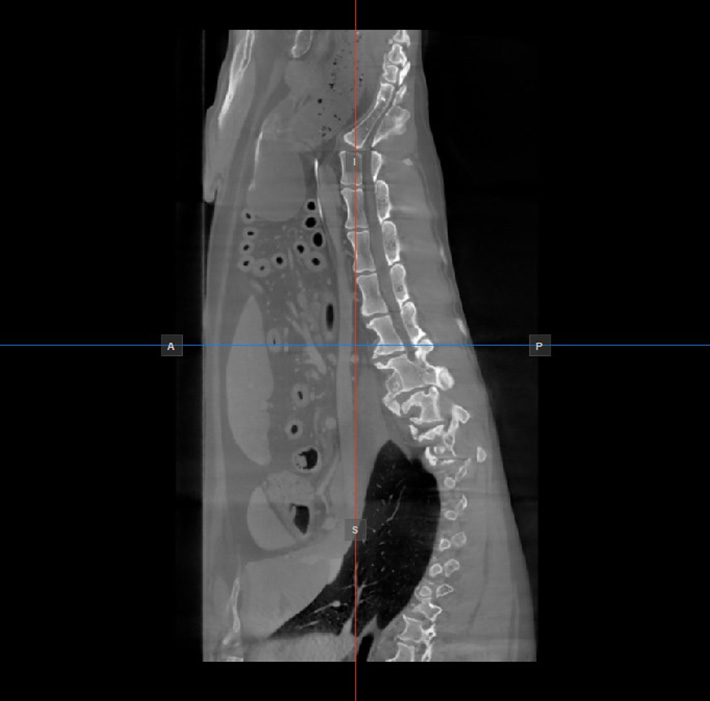

Die Position und der Schnitt der beiden anderen Bildebenen, die im aktiven Viewport nicht dargestellt werden, wird durch zwei vertikale und horizontale Linien angezeigt, die als Slicer bezeichnet werden. Die Endpunkte jedes Slicers sind mit einem Buchstaben gekennzeichnet, der der entsprechenden Richtung/Seite des 3D-Volumens entspricht, basierend auf dem RAS-Koordinatensystem.

Auf jedem 2D-Viewport werden nur vier der verfügbaren sechs Seiten angezeigt. Die Beschriftungen und die entsprechenden Seiten sind wie folgt:

Patient rechts (R), zeigt die rechte Körperseite an

Patient links (L), zeigt die linke Körperseite an

Anterior (A), zeigt die Vorderseite des Körpers an

Posterior (P), zeigt die Rückseite des Körpers an

Superior (S), zeigt die Oberseite des Körpers an

Inferior (I), zeigt die Unterseite des Körpers an